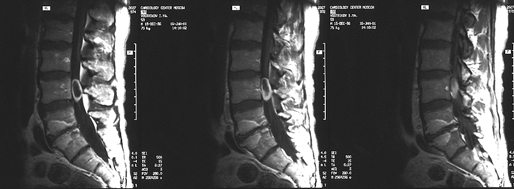

Диагноз уточняется с помощью МРТ, введение контрастного вещества улучшает визуализацию границ опухоли (рис. 1), хотя окончательно наличие четкой границы со структурами спинного мозга и, соответственно, возможность радикального удаления опухоли устанавливаются только в ходе операции.

Рисунок 1. Интрамедуллярная опухоль (астроцитома) шейного отдела спинного мозга (МРТ с контрастным усилением, Т1-взвешенные изображения)